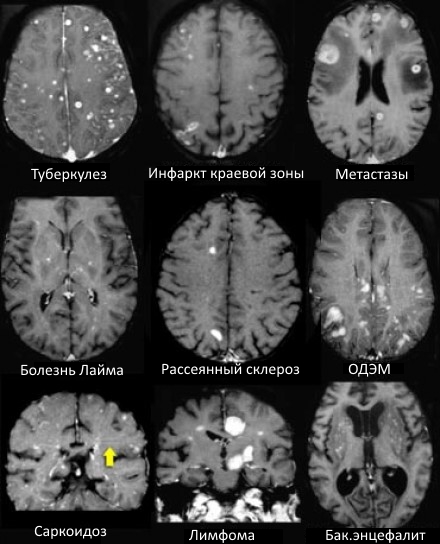

Магнитно-резонансная томография (МРТ)

МРТ позволяет получать детальные изображения структуры мозга, выявлять уменьшение объема ядер, изменения плотности тканей и наличие патологических очагов. В последнее время особое значение приобретают функциональные томографии, которые позволяют наблюдать активность структур при выполнении различных задач.

Нейровизуализация в диагностике и мониторинге терапии

Современные исследования используют МРТ и DTI (диффузионную тензорную визуализацию), чтобы оценивать степень повреждения и динамику изменений. Это помогает не только в постановке диагноза, но и в подборе наиболее эффективных методов лечения.